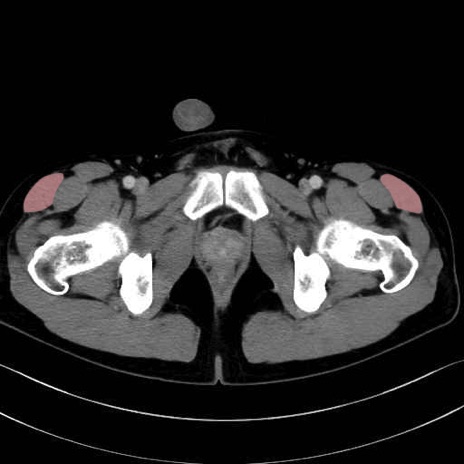

大腿筋膜張筋 (Tensor fasciae latae)